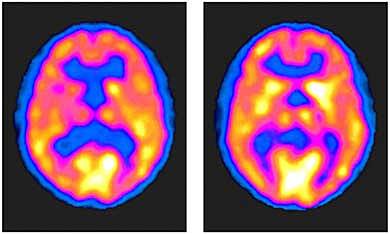

• Tomografía por Emisión de Positrones

Tomografía por Emisión de Positrones

Las pruebas de medicina nuclear también se perfeccionaron con el desarrollo de la tomografía por emisión de positrones (PET).